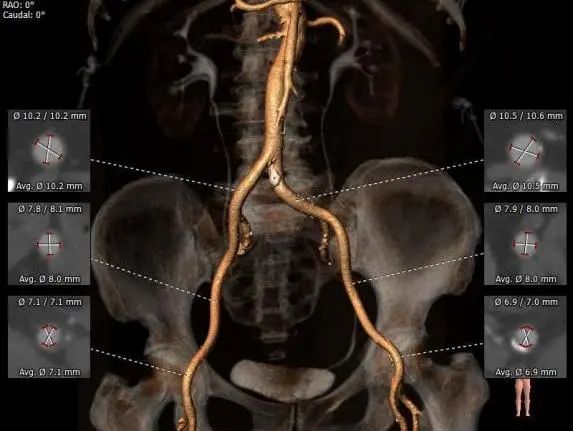

4.外周入路走行及内径可,未见明显狭窄,左股穿刺区少量钙化,入路穿刺规范操作,小心通过,避免入路血管损伤及相关并发症。

外周入路评估

1.右侧股动脉为主入路,左侧为辅助入路,使用20F大鞘。